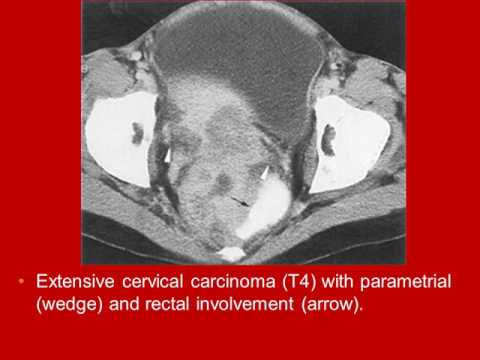

Whole Body Computed Tomography Female Pelvis video book lecture